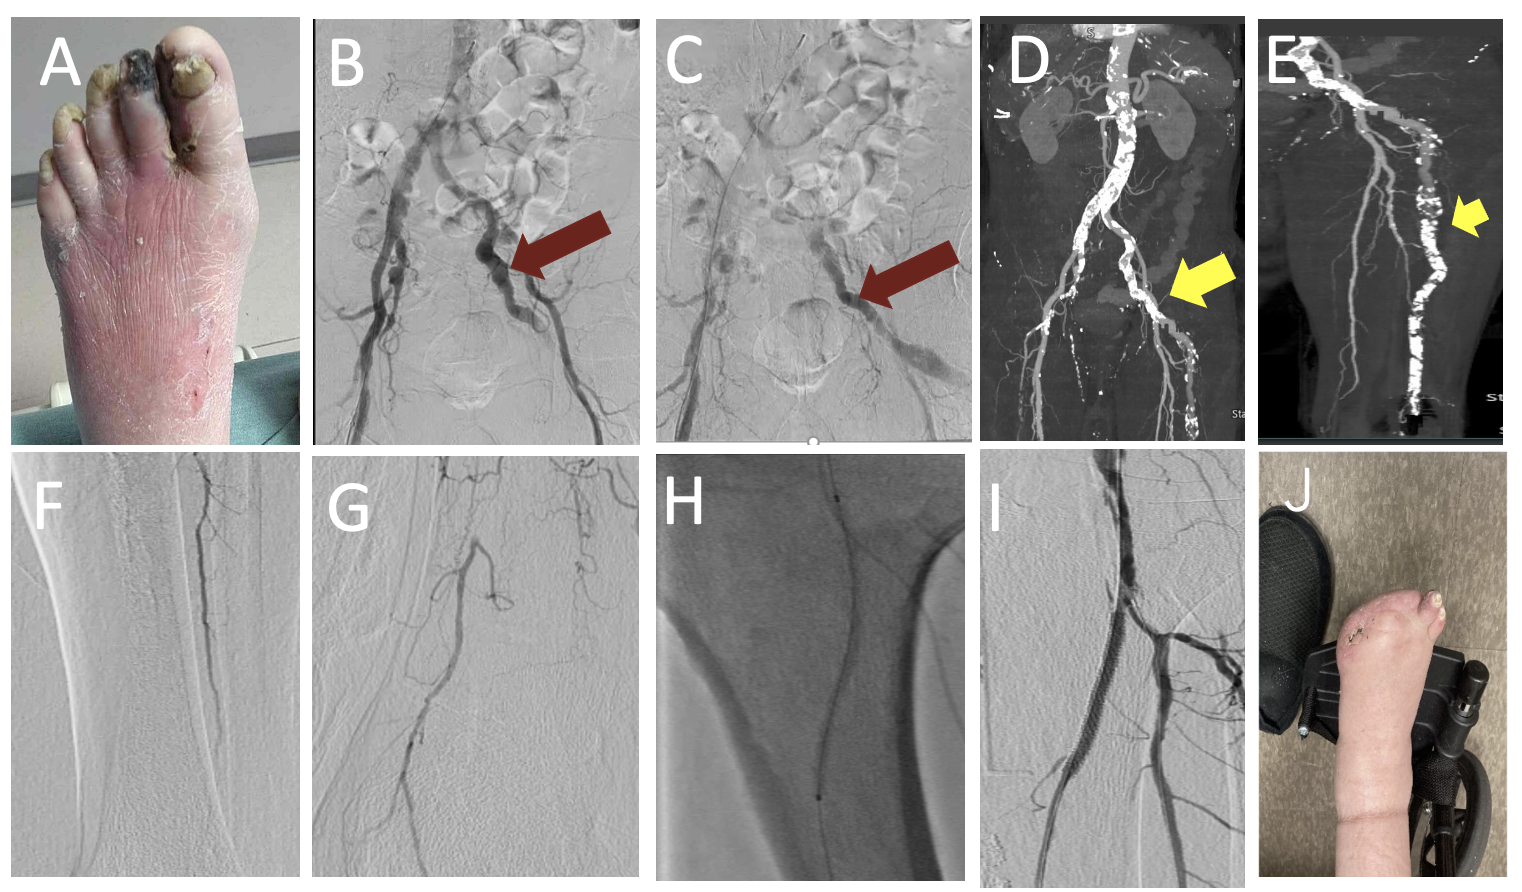

A 77-year-old man with a history of coronary artery disease, hypertension, ongoing heavy smoking, and cirrhosis presented with dry gangrene of the first and second toes (Figure 2A). The patient underwent angiography with planned intervention of the left lower extremity. The inflow images showed abnormal flow in the left internal iliac artery with a diminutive superficial femoral artery (Figures 2B and 2C, Videos 2A and 2B). At this point, the procedure was aborted and a computed tomography (CT) runoff was obtained for additional procedural planning. The CT confirmed the presence of a persistent sciatic artery with severe calcific popliteal and infrapopliteal disease (Figures 2D and 2E).

The following day, the patient returned to the angiography suite. We placed a 65-cm 6F Terumo sheath via the internal iliac artery into the persistent sciatic artery that fed the lower leg (Video 2C). The peroneal was wired antegrade with a 0.014-inch Gladius Mongo wire (Asahi) through a 0.018-inch CXI crossing catheter (Cook Medical). A distal injection through the CXI catheter in the peroneal artery confirmed true luminal position and allowed for visualization of a small reconstituted posterior tibial (PT) artery at the ankle (Figures 2F and 2G, Video 2D). Next, we performed laser atherectomy of the popliteal into the peroneal. This was followed by intravascular ultrasound imaging and nominal ballooning of these vessels.

We then treated the PT CTO using retrograde access into the patent distal vessel. The PT was traversed with retrograde wiring using external ultrasound navigation. Kissing balloon dilation was performed into the peroneal and PT arteries. Subsequent stenting of the proximal PT was performed with 3.5 x 38-mm drug-eluting stent. Completion angiography was performed, and the patient’s wound healed after minor amputation (Figures 2H-J, Video 2E).